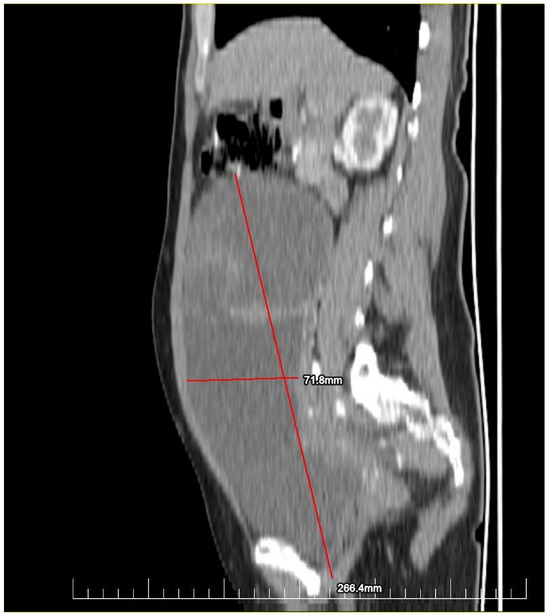

This case report details the presentation, diagnosis, and management of a 44-year-old female who experienced a relapse of colonic cancer with peritoneal carcinomatosis in 2021, two years after the initial diagnosis. The patient exhibited specific symptoms indicative of disease recurrence. In 2019, the patient underwent surgical resection and received adjuvant chemotherapy for colonic cancer. Despite an initial period of remission, in 2021 she presented with symptoms such as abdominal distension, persistent abdominal pain, and changes in bowel habits. Imaging studies, including CT scans, confirmed the presence of peritoneal carcinomatosis, indicating a relapse of colonic cancer along with two suspected tumorous formations localized in the ovaries (Figure 1 and Figure 2). Upon relapse, the patient underwent a thorough diagnostic workup, including imaging studies and tumor marker assessments. Elevated levels of carcinoembryonic antigen (CEA) of 5.44 ng/mL and CA-19-9 of 58 U/mL were observed, supporting the diagnosis of colonic cancer recurrence with peritoneal carcinomatosis.

Figure 2.

Preoperatory sagittal view of a CT image presenting a giant ovarian mass.